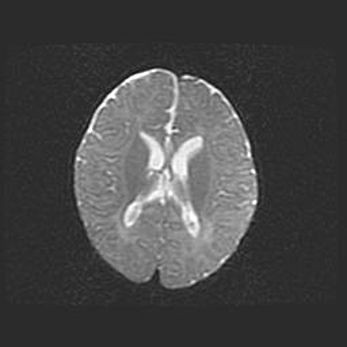

Наружная гидроцефалия с возможной атрофией височных областей.

Возраст: 28 дней

Вес: 3670 г

Пол: мужской

Окружность головы: 38 см

Срок гестации: 40 недель

Гидроцефалия головного мозга у новорожденных – это заболевание, которое характеризуется скоплением избыточного количества спинномозговой жидкости в желудочковой системе головного мозга в результате затруднения её перемещения от места выработки к месту поглощения в кровеносную систему или вследствие нарушения абсорбции. При открытой наружной форме гидроцефалии у новорожденных расширяются и переполняются субарахноидные пространства.

При нормотензивных  формах,  которые,  как  правило,  являются  следствием  перенесенных ишемических  повреждений  паренхимы  мозга,  возможно  сочетание микроцефалии  с нормотензивной гидроцефалией. В основе данных изменений лежит атрофия больших полушарий с преимущественной  локализацией  в  лобно-височных  областях.